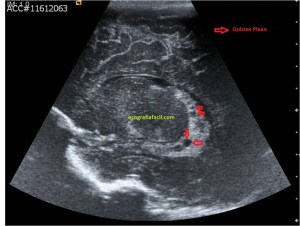

En la imagen 3 ves una imagen de un lipoma, mide 7 cms, la huella de la sonda mide 5cms, la «panoramic view» posee una regla centimetrada que sigue el contorno de la imagen, justo en la profundidad de la misma y lo marca la flecha amarilla. La profundidad la marca la flecha roja y la flecha blanca marca el rango centimetral de los 5cms, fíjate que la línea blanca es ligeramente mayor cada 5 cms. Sirve de referencia, como en la imagen 4 donde ves una colección en el glúteo de más de 10 cms.